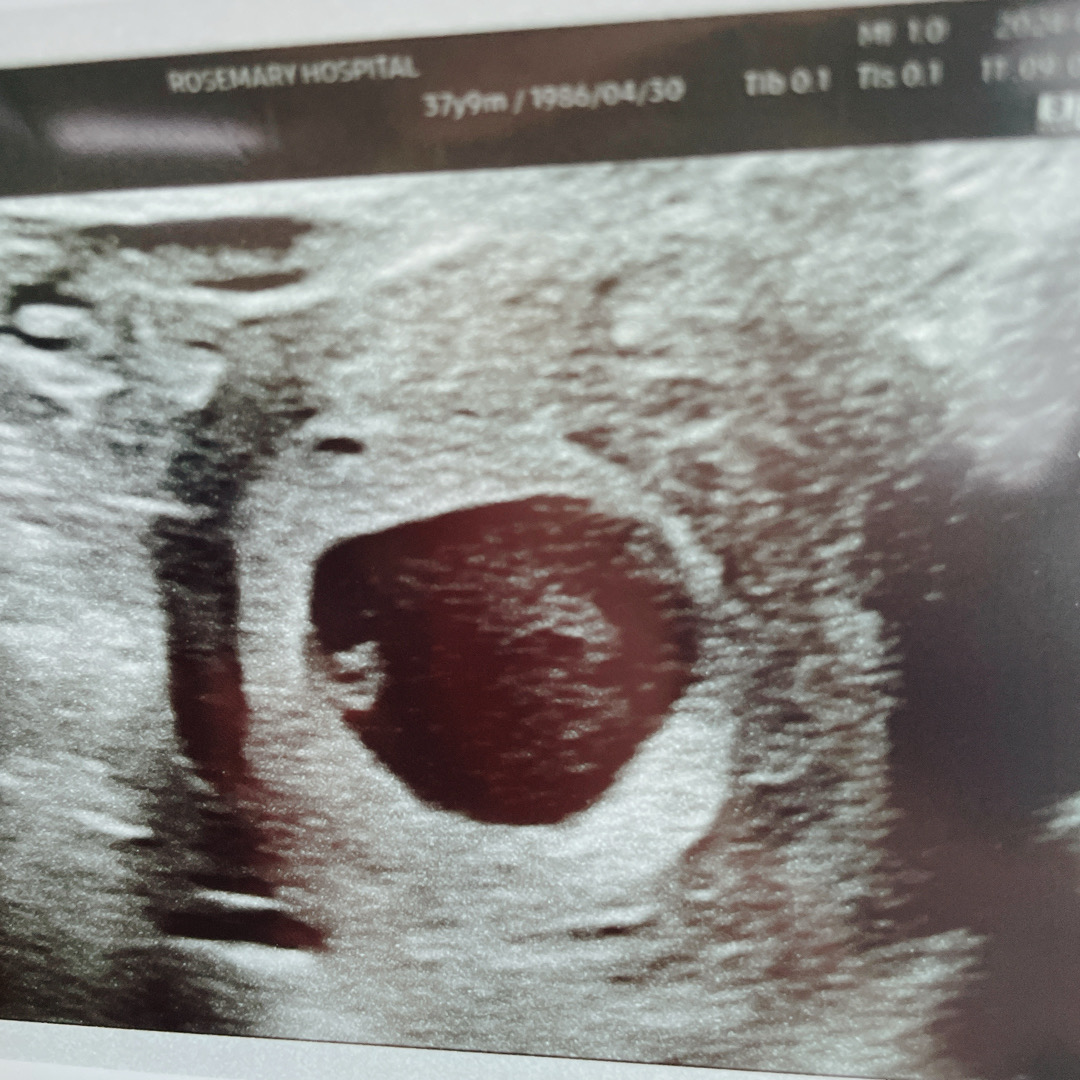

오늘 심장소리 들었어요~!

인터넷에서만 보던 다이아몬드 반지!! 6주2일인데 저 작은 심장이 뛰더라구요 ㅠㅠ 진료실 들어가기전에 얼마나 걱정하고 있었는지.. 심장소리 듣는데 너~무 신기하고 이번에는 잘 지키고 싶어요~!!